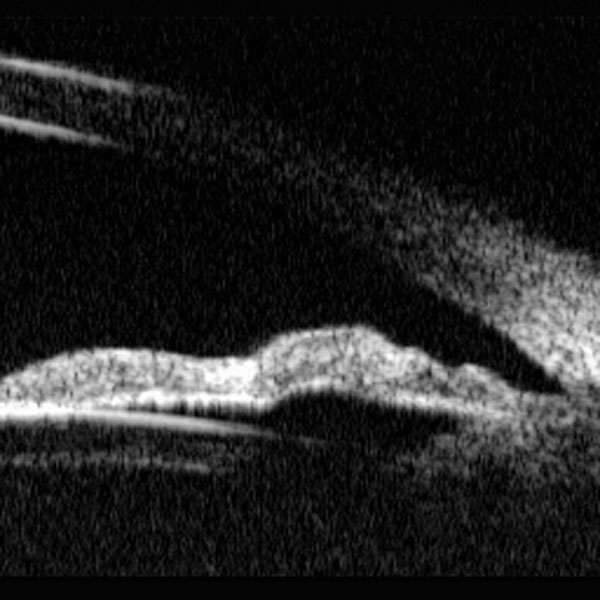

El aspecto de estos tumores en la exploración con BMU es el de una masa sólida de reflectividad media y uniforme apreciándose una atenuación progresiva de la imagen (FIGS 6.23.b, 6.24.b, 6.25.b, 6.26.b, 6.28.b y 6.29.b). Practicando cortes radiales y tangenciales puede determinarse la localización, el tamaño y los límites del tumor. Aunque la resolución de las imágenes no permite la delimitación de la masa tumoral a nivel celular el cambio de reflectividad permite determinar con precisión el límite entre el tumor y el tejido normal (FIGS 6.23.c, 6.24.b, 6.25.c, 6.26.b, 6.26.c y 6.27.c)

F06_25_2.jpg (61330 bytes)

FIGURA 6.25.b: Corte radial de BMU. Engrosamiento en la parte anterior del cuerpo ciliar que diseca la mitad anterior de la raíz del iris. La periferia del iris está abombada hacia adelante. La zona afectada tiene una reflectividad media baja que permite diferenciarla de los tejidos circundantes (flechas). (I.N.G.O.)

F06_25_3.jpg (64869 bytes)

FIGURA 6.25.c: Corte tangencial de BMU a nivel de los procesos ciliares. Se observa a nivel de la raíz del iris una zona engrosada de menor ecogenicidad que el tejido circundante, que está ocupando el ángulo. En esa zona se pierde la línea hiperreflectiva del epitelio pigmentario. En los procesos ciliares contíguos se observa un engrosamiento y desflecamiento de los bordes y menor reflectividad (flechas). (I.N.G.O.)

FIGURA 6.25.d: Corte radial de BMU. Un control 12 meses después no demuestra cambios significativos en la exploración bioultrasónica.

Las características de la lesión y sobre todo sus dimensiones, valoradas mediante BMU, aconsejan su seguimiento. (I.N.G.O.)